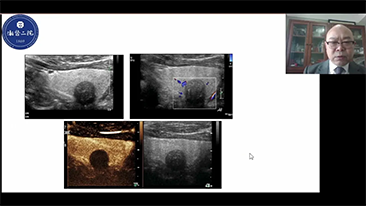

ImĂĄgenes generales

Las soluciones de imĂĄgenes generales de Resona de Mindray ayudan al personal clĂnico a realizar diagnĂłsticos y obtener resultados de tratamiento mĂĄs precisos y eficientes a travĂ©s de sondas para aplicaciones de subdivisiĂłn integrales y herramientas de aplicaciĂłn clĂnica eficientes.